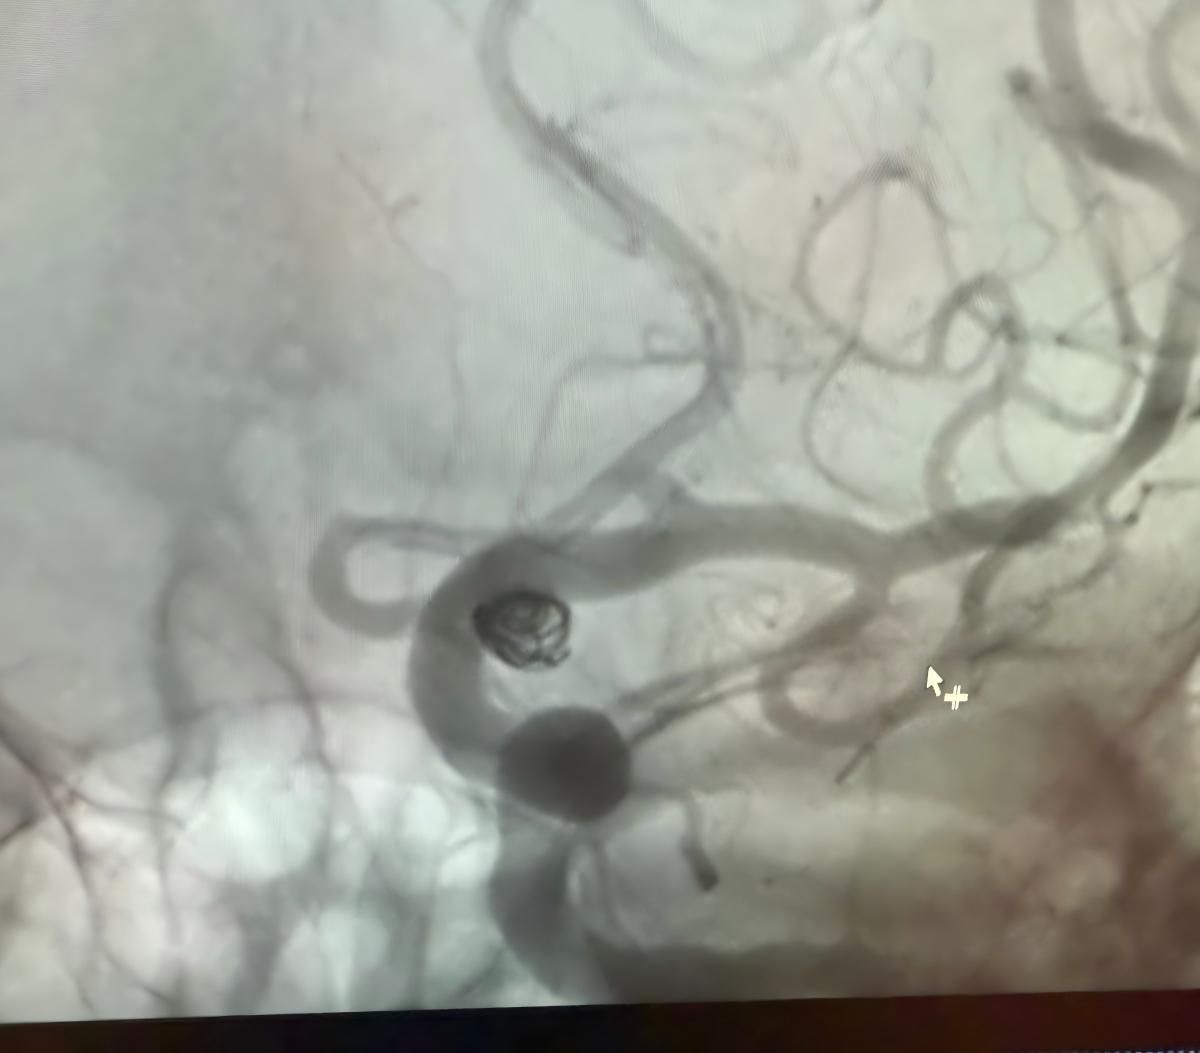

Siamo lieti di condividere una recente procedura di successo presso Clínica Alma Mater, Medellín, eseguita dal Dr. Jorge Mutis.

Il trattamento ha utilizzato la Nuva®Deviatore di flusso (TJED-D 5.0-14), Perdenser®Bobina 3D e Fepass®Microcatetere (TJMC18 Plus) per un aneurisma dell'arteria comunicante posteriore.

Il dottor Mutis ha evidenziato l'eccellente visibilità del dispositivo e ha notato che il recupero è stato regolare. Ha espresso grande soddisfazione per l'esito finale.